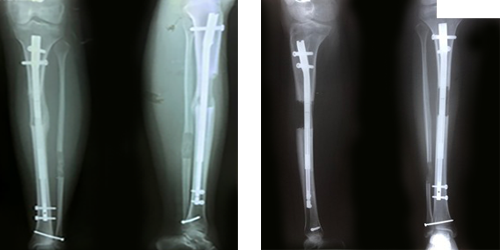

إطالة الطرف فوق تركيب مسمار نخاعي داخلي غيرذاتي  التطويل LON

هي تقنية جراحية تساعد المرضى الذين لا يرغبون في الحصول على تركيب جهاز تثبيت خارجي لفترة طويلة على عظامهم. ونستخدم أداة التثبيت الخارجية فقط خلال فترة الإطالة بينما يوجد مسمار نخاعي  داخل العظم ، ثم بعد الانتهاء من الإطالة نقوم بتثبيت  المسمار النخاعي داخل العظم ونقوم بإزالة المثبت الخارجي  ، بحيث يستطيع المسمار النخاعي حماية العظم الضعيف الذي تم تشكيله حديثًا حتى يتم إلتئامه  بالكامل في غضون 4إلي 5 أشهر.من مزايا هذه العملية أن فترة التثبيت الخارجي بأكمله يستغرق حوالي من 10إلي 12 أسبوعًا وأنه أرخص بكثير من القيام بالمسامير  النخاعيه الداخلية  ذاتية التطويل .

من عيوبها اننا نحتاج إلى اجراء عمليتان علي الاقل : واحدة لإدخال المسمار النخاعي وجهاز المثبت الخارجي والأخرى للتثبيت النهائي المسمار النخاعي وإزالة المثبت الخارجي بعد الانتهاء من الإطالة الكبري .

ميزتها أنها أرخص فى التكلفه من طريقة المسمار الداخلي بالريموت كنترول مع تقليص فترة التثبيت الخارجي .